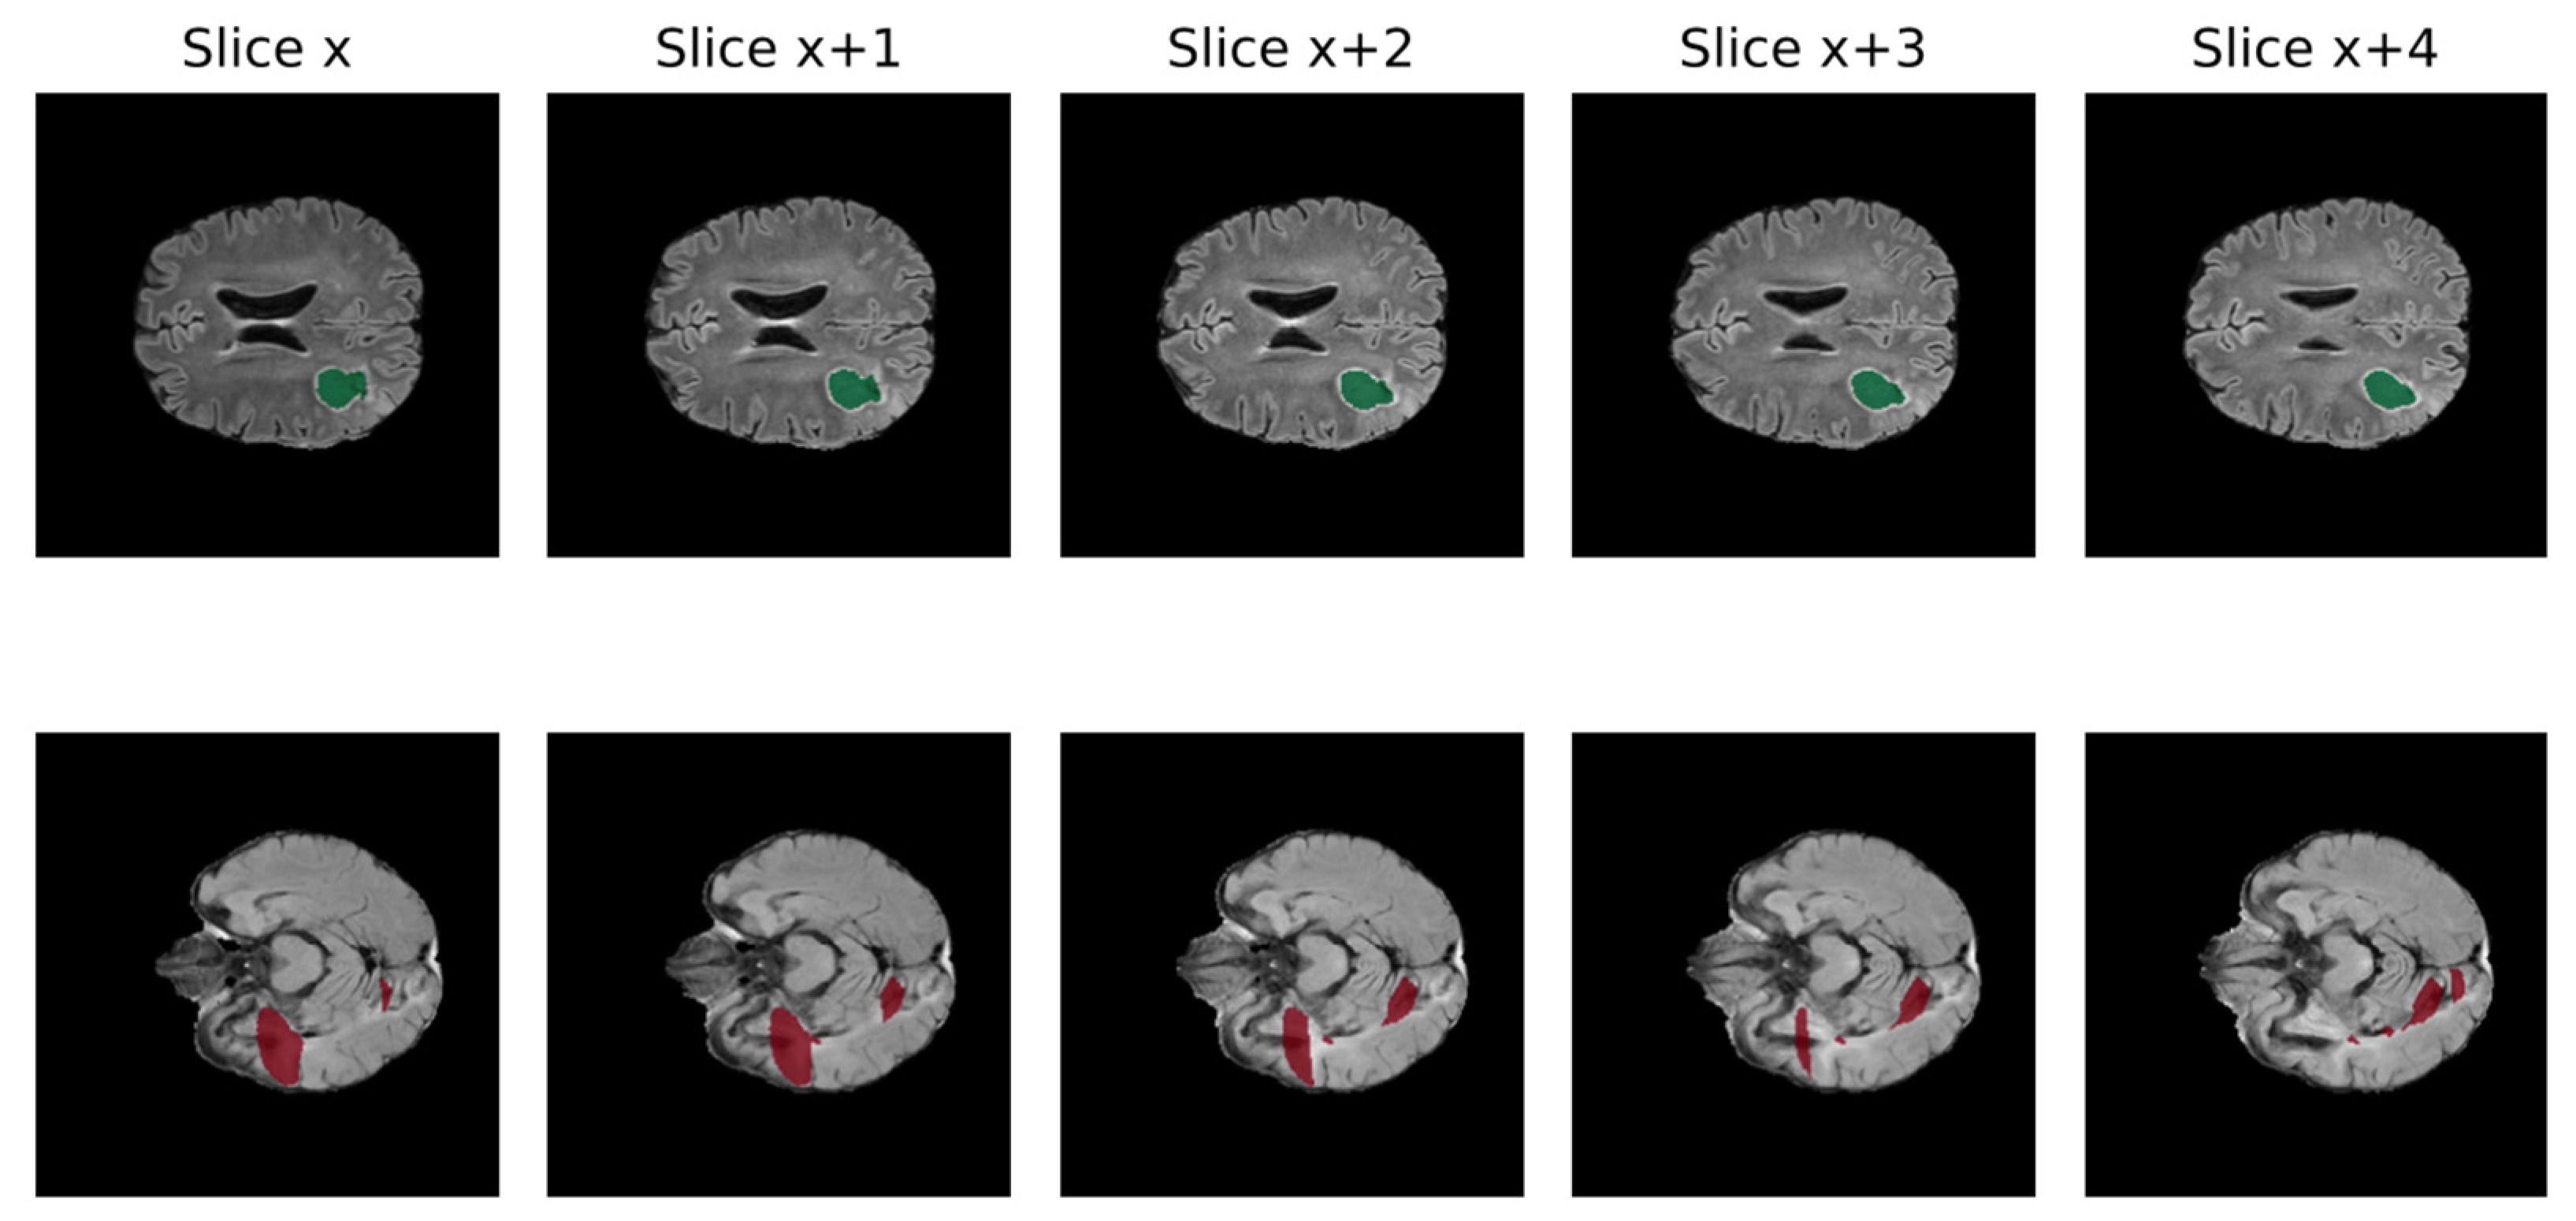

- Reina, G.A.; Panchumarthy, R.; Thakur, S.P.; Bastidas, A.; Bakas, S. Systematic Evaluation of Image Tiling Adverse Effects on Deep Learning Semantic Segmentation. Front. Neurosci. 2020, 14, 65. [Google Scholar] [CrossRef]

- Huang, B.; Reichman, D.; Collins, L.M.; Bradbury, K.; Malof, J.M. Tiling and Stitching Segmentation Output for Remote Sensing: Basic Challenges and Recommendations. arXiv 2018, arXiv:1805.12219. [Google Scholar] [CrossRef]